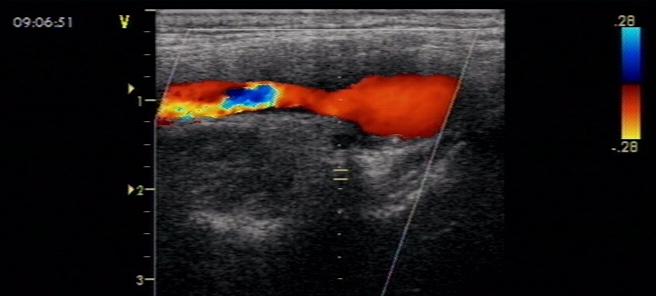

那么发现斑块是否要处理呢?这主要取决于是否有临床症状、斑块大小、稳定性以及颈动脉狭窄程度。颈动脉斑块可以没有任何临床症状,也可以出现脑供血不足、短暂脑缺血发作甚至缺血性卒中等严重后果;一般来讲,如果狭窄程度在50%以下且没有临床症状,这时候以改变不良生活方式为主,包括:控制血糖、血压、戒烟戒酒、合理运动、减肥等,必要时使用他汀类药物;如果狭窄在50%以上且有症状,或狭窄超过70%,不管有无临床症状,都应考虑采用药物+手术治疗方案,包括他汀+抗血小板等药物治疗,颈动脉内膜剥脱术(CEA)或颈动脉支架成形术(CAS)等。